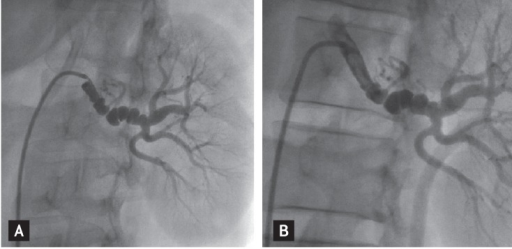

What's the Diagnosis?